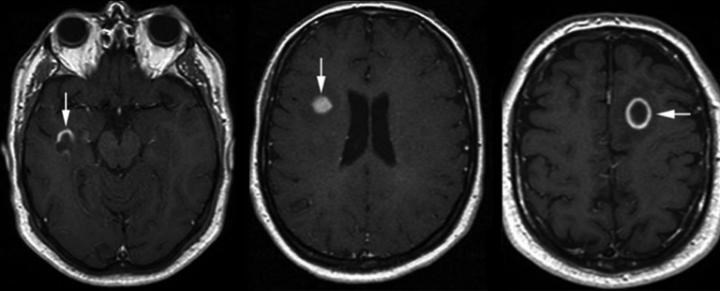

Gadolinyum tutulumu ve aktif lezyonlar

Gadolinyumlu (Gd’lu) MRG, MS’te aktif lezyon saptamada oldukça duyarlıdır ve kan–beyin bariyeri yıkılımını gösterir. Gd tutulumu genellikle 2–6 hafta sürer; seyrek olarak 3–4 aya kadar uzayabilir. Gd tutan lezyonların yaklaşık %80’i T1 ağırlıklı görüntülerde hipointens izlenir; bunların %40’ından daha azı kalıcı “kara delik” haline gelir.

T1 hipointens lezyon, yalnızca kalıcı doku kaybını değil, ödem veya parsiyel remyelinizasyon sürecini de yansıtabilir. Gd tutulumu açısından en sık görülen paternler:

- Nodüler tutulum (%68),

- Halka şeklinde tutulum (%23),

- Diğer paternler (%9).

Halkasal tutulum, lezyonun merkezinde parsiyel remyelinizasyonun olduğu veya KBB yıkılımının kısmen onarıldığı; çevresinde ise inflamasyonun sürdüğü durumlarda görülür. Nodüler tutulum gösteren lezyonlar zaman içinde küçülme eğilimindedir. Bu paternlerin hiçbiri tek başına MS’e özgü değildir; tek istisna, “açık halka” görünümüdür. Açık halka tutulumu, MS lezyonunu bazı tümör ve enfeksiyonlardan ayırmaya yardımcı olabilir; açık kısım tipik olarak gri maddeye dönüktür.

Aktif lezyonların büyük kısmı klinik olarak sessizdir ve Gd tutulumu uzun dönem engelliliğin doğrudan göstergesi değildir. Buna karşın, özellikle hastalığın erken döneminde aktif lezyonların gösterilebilmesi, erken tanı açısından önemli avantaj sağlar. Yüksek doz steroid tedavisi Gd tutulumunu baskılayabilir; yüksek doz Gd verilmesi ise aktif lezyon saptama duyarlılığını artırır.

İMG – MRG-7: Gd tutan aktif lezyon.